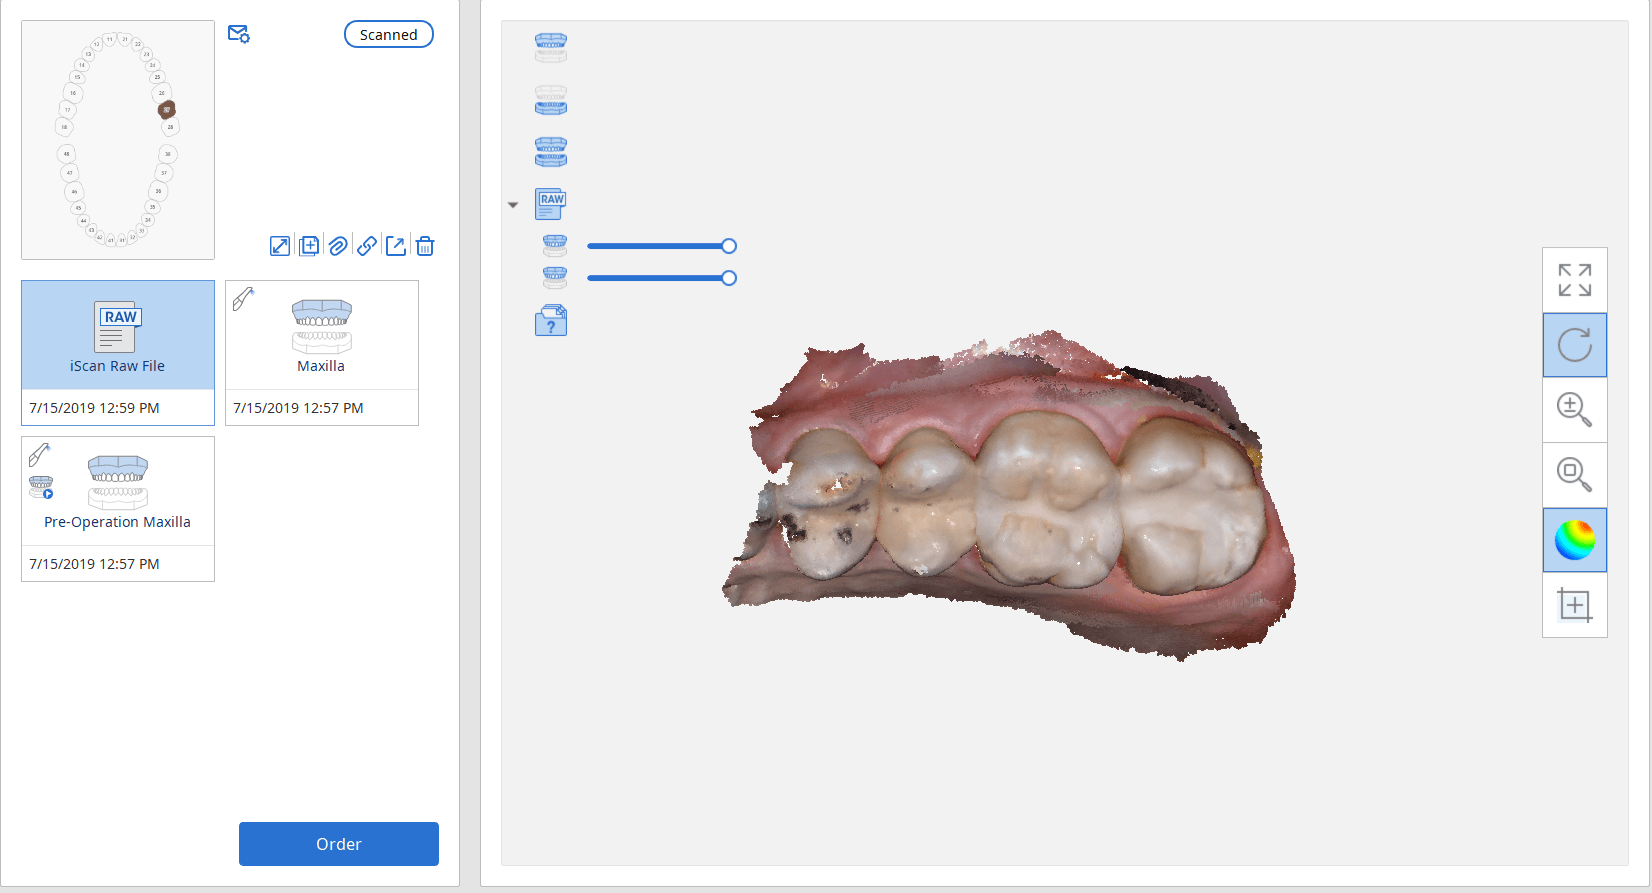

July 18, 2019There are multiple ways one can capture the bite for a patient. In this clinical case, we focus on the easiest way to capture two bites (one in maximum intercuspation […]